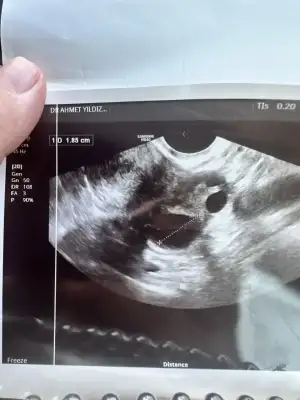

tamam canım at bakalımEvet canım verdi ultrason kağıdı onunda fotografını atayım birazdan ben anlamıyorum yorumlayamadım

Rahmin kalınlaşması iyi canım benimki inceymis doktor ilaç verebilirim dediEvet canım verdi ultrason kağıdı onunda fotografını atayım birazdan ben anlamıyorum yorumlayamadım

Hadi hakkında hayırlısi olsun canm inşallah kandada cikarŞimdi doktordan çıktım canım yumurtan yanlış çatlamış dedi ama rahmin kalınlaşmış dedi kanda bakalım dedi yoksada tedavi verdi çok ilgilendi yumurtam kaliteliymiş sorun yokmuş 2 ay da olması yüksek dedi olmazsa rahim filmi çekeriz dedi moralim düzeldi valla kür falan verdi bana onları yapıcam kan sonucumda saat 16 da çıkacak

İnşallah hamilesindir kuzum benim haberdar et mutlaka biziŞimdi doktordan çıktım canım yumurtan yanlış çatlamış dedi ama rahmin kalınlaşmış dedi kanda bakalım dedi yoksada tedavi verdi çok ilgilendi yumurtam kaliteliymiş sorun yokmuş 2 ay da olması yüksek dedi olmazsa rahim filmi çekeriz dedi moralim düzeldi valla kür falan verdi bana onları yapıcam kan sonucumda saat 16 da çıkacak